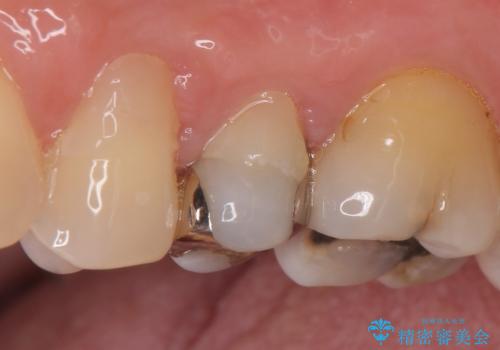

- 左上の奥歯がズキズキ痛むので診て欲しいといらっしゃった方の症例です。

診査の結果左上5、6番の歯が痛みの原因であり、神経の保存が難しかったため根管治療を行いました。

痛みの消失を確認後、オールセラミッククラウンによる補綴を行いました。